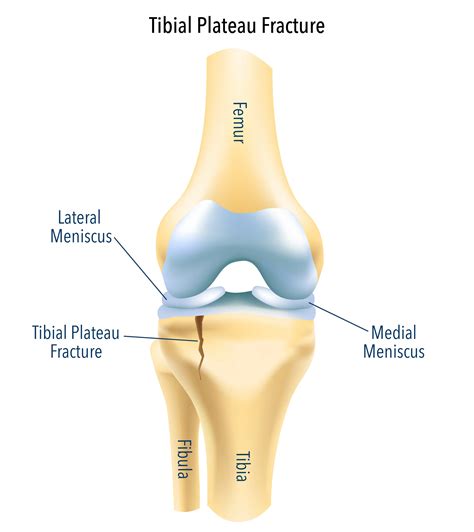

The tibia is the larger of the two bones in your lower leg, and its top surface, the tibial plateau, is divided into two sections: the lateral (outer) and the medial tibial plateau (inner). This surface is covered in articular cartilage, a smooth, tough tissue that allows the femur to glide seamlessly over the tibia during movement. The medial side is generally larger and slightly concave compared to the lateral side, which helps accommodate the curvature of the medial femoral condyle.

• Tibial Plateau Fractures: These are typically caused by high-energy trauma, such as car accidents or falls from heights. A fracture here disrupts the smooth cartilage surface, potentially leading to post-traumatic arthritis.